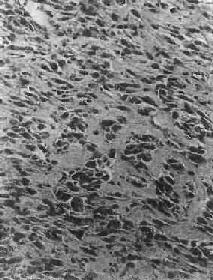

镜下,肿瘤主要由单核基质细胞及多核巨细胞等两种细胞组成(图17-6),间质血管丰富。基质细胞为梭形、卵圆形或圆形,细胞境界不清楚,常见胞浆突起。细胞核较大,染色质量中等,可具有一个核仁。多核巨细胞常较均匀地散布在基质细胞之间,是为本瘤的特点。多核巨细胞的直径常为30~60μm,核数一般为15~20个,最多可达100个以上,常聚集在细胞的中央。核的形态与单核基质细胞相似。细胞边界不规则,但分界较清楚,胞浆丰富,略呈嗜碱性,有时还可见含大量脂类的泡沫细胞。本瘤间质血管丰富,有多少不等的胶原纤维。肿瘤本身无成骨现象,但有时见有类骨组织及新生骨小梁,常见于纤维组织的周围,可能是一种反应性新骨形成或病理性骨折后形成的骨痂。

图17-6 骨巨细胞瘤(Ⅰ级)

肿瘤由大量基质细胞和多核巨细胞两种细胞组成 ×175